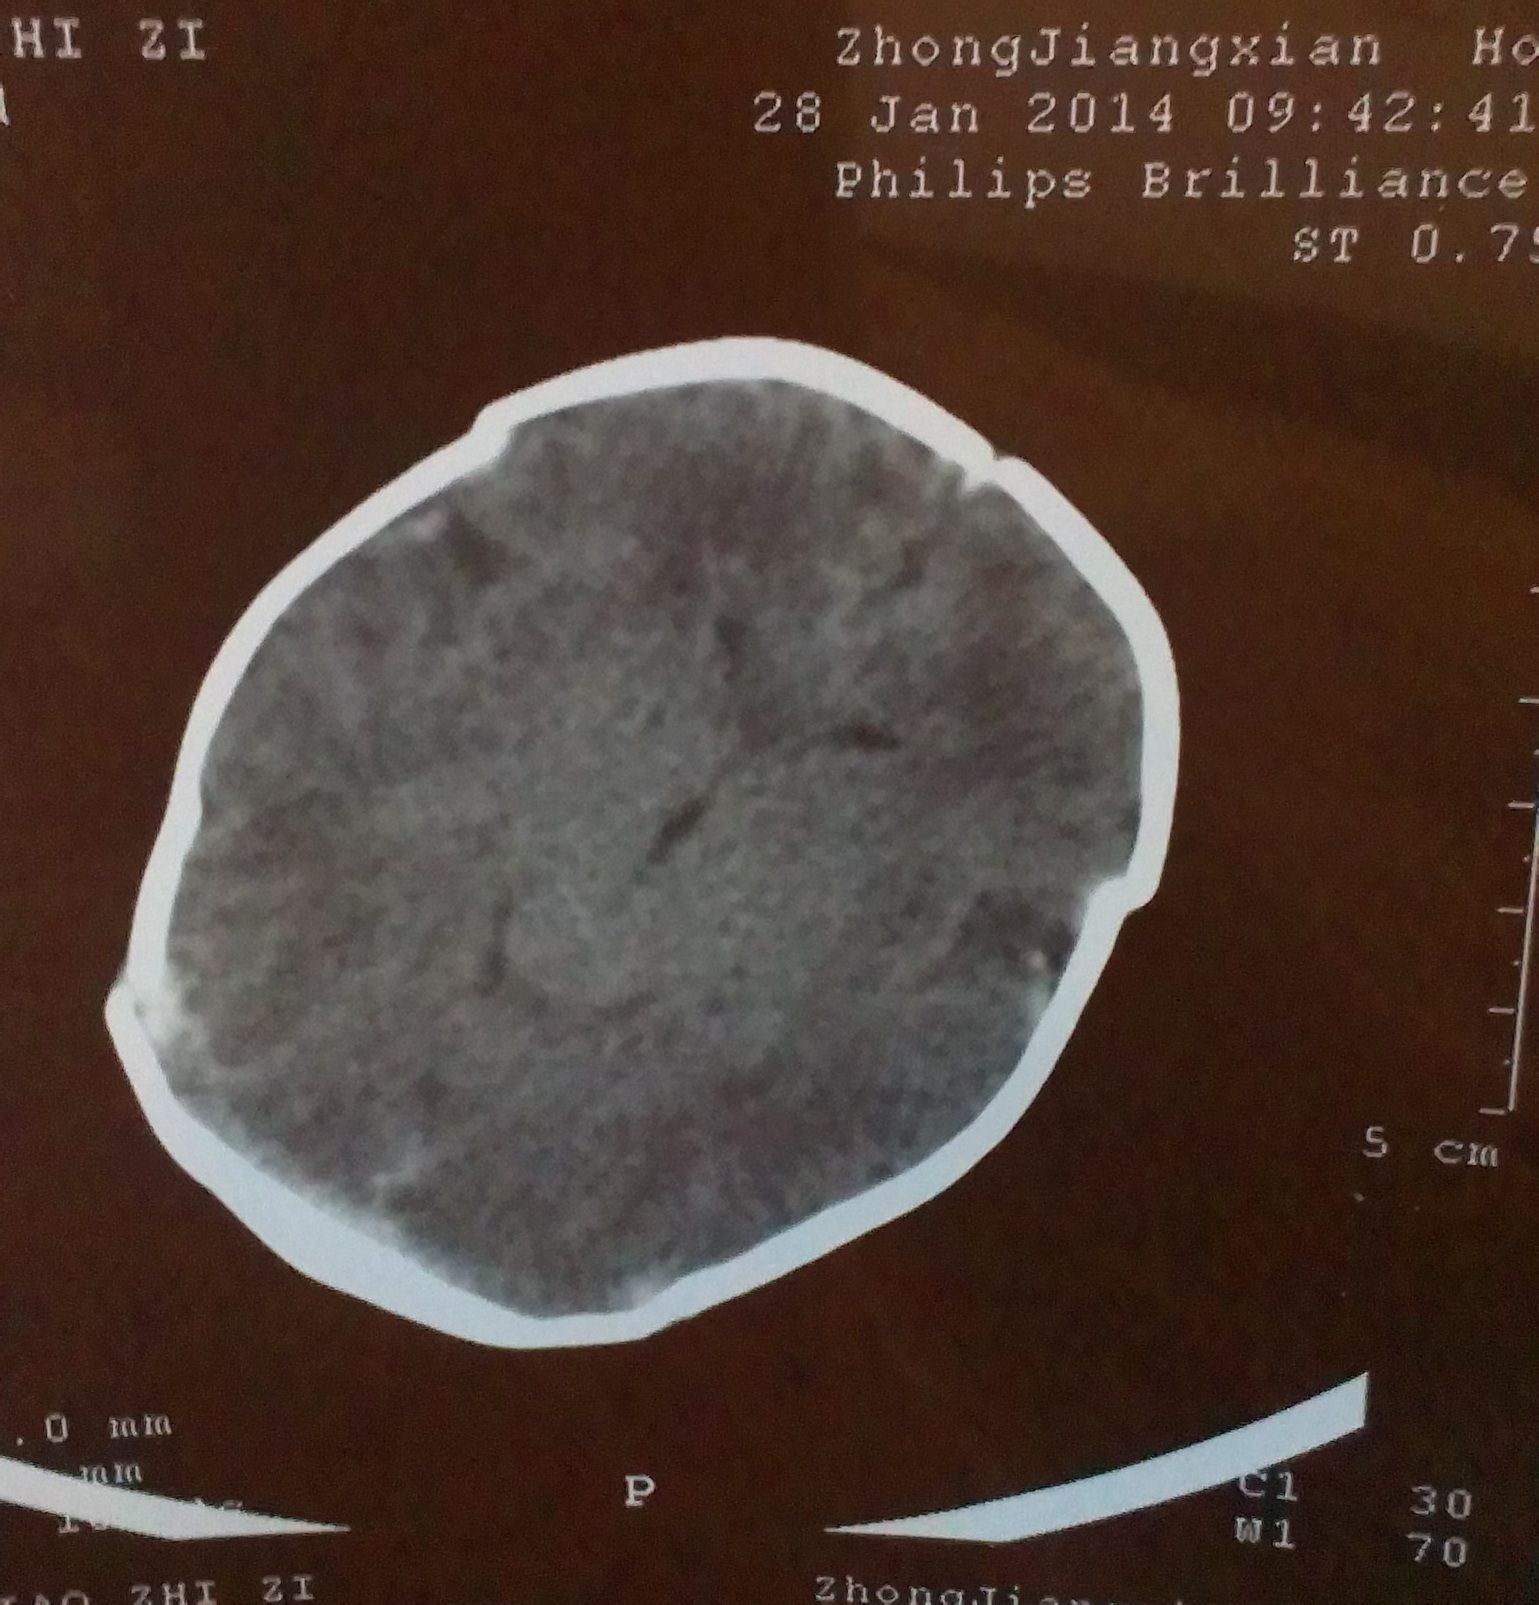

跪求能看懂脑部CT片子的专业人士帮忙,请帮我看一下,我小孩的脑部是什么问题 小孩是36周早产,这是 出生后第四天拍的CT片子,请帮我看一下,脑部有什么问题,严重吗?我应该怎么办,,,不胜感激,,,好人一生平安,感谢。 点击展开 匿名用户 2014-02-25 19:09 为您推荐: 其他回答 你好根据CT上的表现有蛛网膜下腔出血的表现,建议如果小孩子有不爱哭闹或者吃奶不好活动不好等情况及时复查一个颅脑CT或者MRI看看 丑梦月_TNVJ 2014-02-25 22:12 相关问题 宝宝是36周+2的早产儿,年龄25天了,医生要给宝宝照脑部CT,请问这么小照脑部CT 宝宝33周早产,已在保温箱5天了,检查均无问题(除脑部CT),现在每隔3小时吃一次,每次25mL 请问有谁的早产儿脑部发育不成熟用过申捷注射液?对大脑能够发育到什么程度?CT检测:脑部发育欠完善